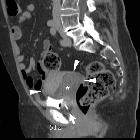

Giant

fibroepithelial polyp of the uterine cervix. Portal venous (f,g) and excretory (h,i) phase acquisitions showed persistent progressive enhancement in the anterior solid portion of the enlarged cervix (arrowheads), absent enhancement in the dorsal hyperattenuating portion (*).